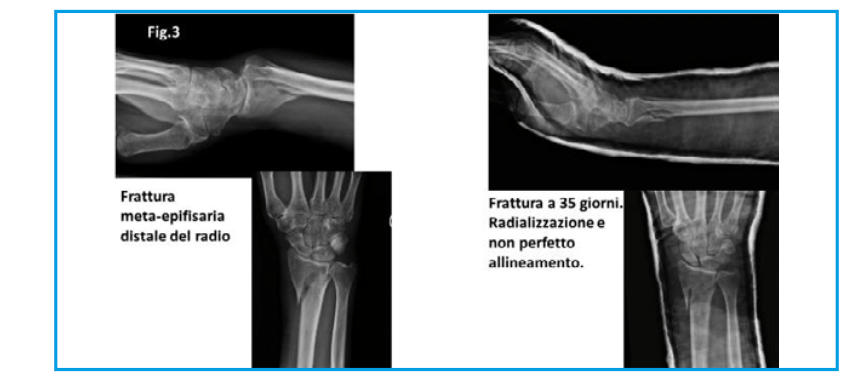

Uomo, età compresa nella decade 50-60 anni, frattura meta-epifisaria distale del polso destro. Controllo in ambulatorio, rimozione gesso e controllo radiologico.

La frattura si presenta in consolidazione viziata, deviata verso il radio e con un già importante callo osseo riparativo. (fig.3)

Operato al 45° giorno; viene sottoposto ad intervento di asportazione del callo osseo riparativo, riduzione della neo-frattura e osteosintesi con placca a basso profilo in titanio nickel-free con raggiungimento di un ideale allineamento anatomico.

Nessuna indicazione per gesso nel post-operatorio, solo bendaggio elastico non adesivo e inizio immediato delle mobilizzazione.